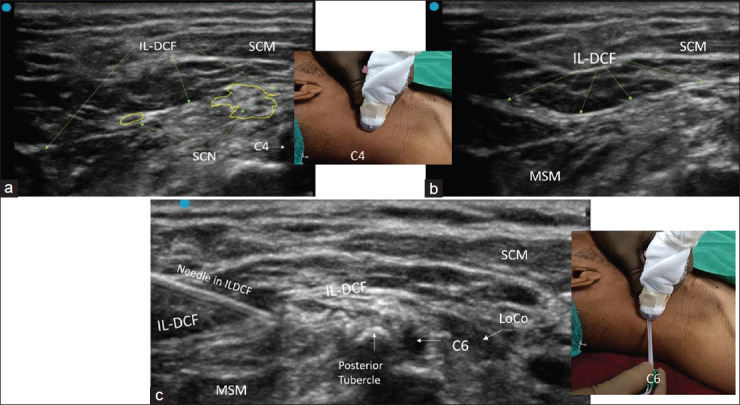

Methods: This cadaveric study (a total of 6 soft-embalmed cadavers and bilateral dissections, i.e. 12 specimens) intended to ascertain the location of SCN within the layers of the IL-DCF. We hypothesized that ultrasonography identification of SCN within the IL-DCF and needle tip positioned between the layers of IL-DCF provide an alternative site for the blockade of the SCN.

Results: After dissection, we described a compact double-layered IL-DCF hosting the SCNs and a specific topographic arrangement at the C4 root with SCN lateral and C4 branches of the phrenic nerve medial to the C4.

Conclusion: We recommend another alternative site for the SCN block at a site in the compact double layer of IL-DCF. We conclude that a caudal site at the exit of SCN from the IL-DCF would be appropriate to perform the intervention.